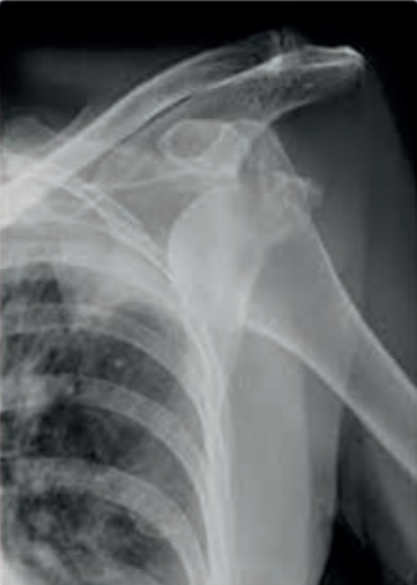

Którą patologię uwidoczniono na zamieszczonym rentgenogramie?

A. Zwichnięcie kości ramiennej.

B. Złamanie nasady dalszej kości ramiennej.

C. Złamanie obojczyka.

D. Stłuczenie łopatki.